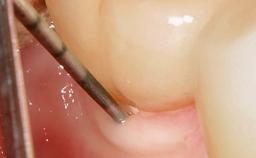

Ridge Preservation and Implant Placement for a Fixed Dental Prosthesis After a Car Accident

It is well known to clinicians that any removal of teeth will, over time, cause the dimensions of the alveolar ridge to be reduced by resorption of the bundle bone and by changes related to external modeling. This development is particularly evident in the crestal region with its thin buccal bone that consists of bundle bone almost entirely. The facial bone will rapidly resorb as blood supply from the periodontal ligament gets disrupted (Araújo and Lindhe 2005). There is no reason why traumatic tooth loss should not have the same consequences. It takes more than achieving implant osseointegration for a treatment outcome to be considered successful. No deficiency of bone or soft tissue is acceptable when an ideal esthetic outcome is the goal. Several articles (Sanz and coworkers 2011; Vignoletti and coworkers 2011) have reported on techniques of improving the alveolar ridge for implant treatment, notably focusing on protecting tissues from resorption.